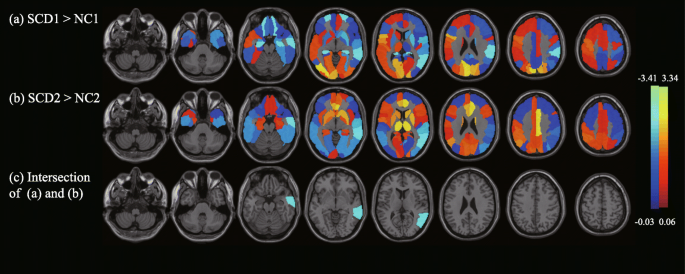

Figure 1 shows the metabolic changes of SCD compared with NC of the 90 ROIs. Figure 1a shows the metabolic changes of the SCD individuals in cohort 1. SCD was significantly hypometabolic in the bilateral superior orbital frontal gyrus and hippocampus, right rolandic operculum, supramarginal gyrus and middle temporal gyrus (MTG), and hypermetabolic in the bilateral calcarine, cuneus, and superior occipital gyrus, left inferior opercular frontal gyrus and rolandic operculum, and right inferior occipital gyrus. Figure 1b shows the metabolic changes of SCD individuals in cohort 2. The SCDs were significantly hypometabolic in the bilateral inferior occipital gyrus lingual gyrus and MTG, right middle occipital gyrus, fusiform gyrus, superior temporal gyrus, and left inferior temporal gyrus and were hypermetabolic in the bilateral anterior cingulate gyrus, paracingulate gyrus, left angular gyrus, right median cingulate gyrus, and paracingulate gyrus. Figure 1c shows the intersection area of the significantly altered area of the two cohorts; only the right MTG (RMTG) was retained in both cohorts 1 (p < 0.05) and 2 (p < 0.001). The RMTG was the only brain area that had significant differences in each subset of the 10 repeated two-fold cross-validations; the details are listed in supplementary Table 1.

The results of SCD glucose metabolic biomarkers based on ROI analysis. In the metabolic comparisons between SCD patients and NCs, this study considered the 90 regions (AAL template) as ROIs and calculated the mean SUVR value of each ROI, which was adjusted for age, sex, and education. Permutation tests 1000 times were used to find significant differences between NC1 and SCD1 as well as between NC2 and SCD2. a and b show the SCD regional changes of 90 ROIs compared with NC, where a NC1 and SCD1 were used from cohort 1, b NC2 and SCD2 were used from cohort 2, and c shows the intersection areas of significantly different regions in (a) and (b). The regions with metabolic changes of SCD are overlaid on the structural MRI template images. Cool colors represent voxels with negative region weights and hypometabolism, and hot colors represent voxels with positive weights and hypermetabolism. Abbreviations: SCD, subjective cognitive decline; ROI, region of interest; NC, normal control; AAL, anatomical automatic labeling; SUVR, standardized uptake value ratio; MRI, magnetic resonance imaging